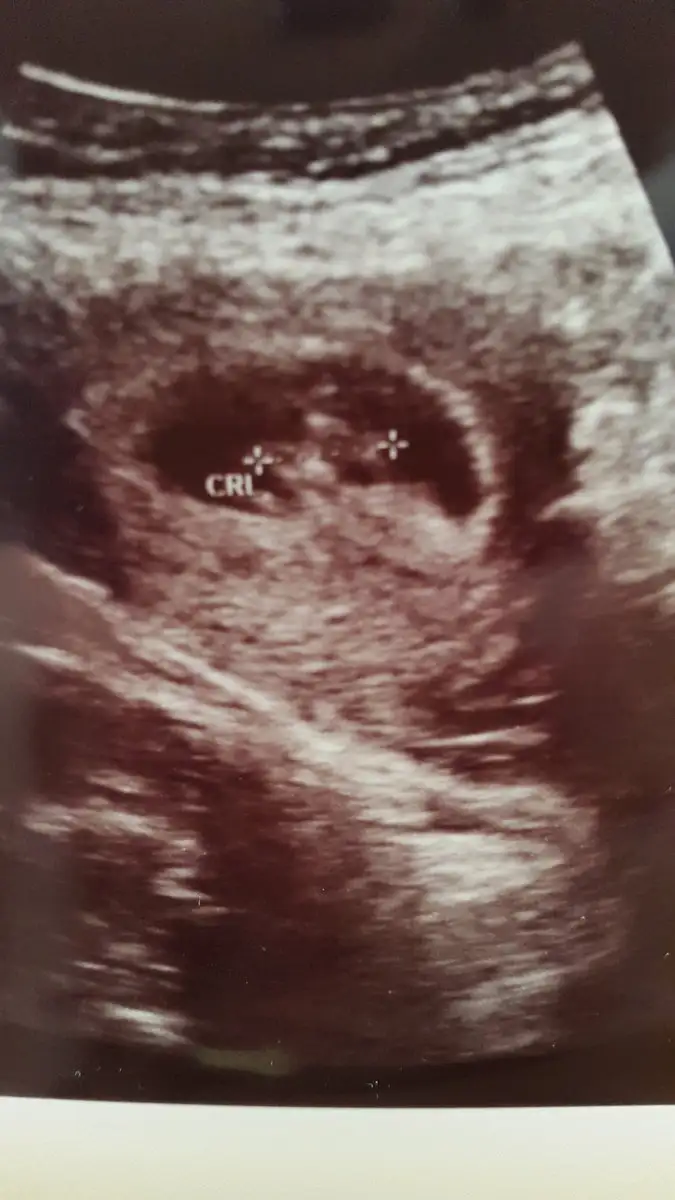

Bana da bakar mısınız tam 8+0 karından bakıldı

Canim baska ilk utrasyon res yokmuBana da bakar mısınız tam 8+0

Maalesef bu ilk ve tekCanim baska ilk utrasyon res yokmu

Bu birz buyuk ama olsun bi tahminde bulunmmi istersen erkege benzetdimMaalesef bu ilk ve tek

Kiz gibi

Aslinda suan 7+6 oldum ama doktora gittigimde 6+5ti canim kalp atisini duyduk o gun 2 gun geriden gelyodu snada masaallahh canim 9 haftalik olmussun heraldeKaç haftalik canım maşallah bebeğine

Sağlıklı büyüsünlerde geriden gelsede farketmez canim 8+4 ümAslinda suan 7+6 oldum ama doktora gittigimde 6+5ti canim kalp atisini duyduk o gun 2 gun geriden gelyodu snada masaallahh canim 9 haftalik olmussun heralde